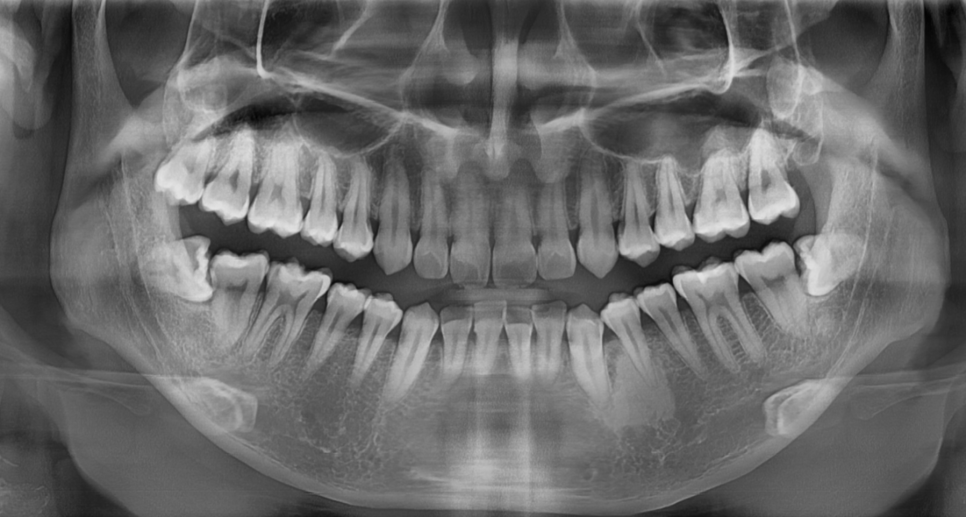

230725 양쪽으로 누워있는 매복 사랑니